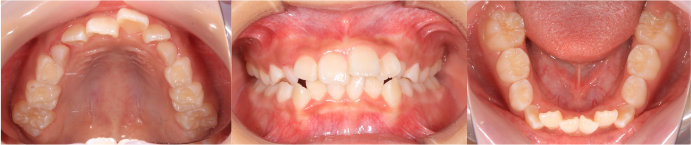

| <治療前> |

|

| <治療後> |

| 主訴 |

前歯が出ている |

| 診断名 |

上顎前突 |

| 年齢 |

8歳 |

| 使用装置 |

マルチブラケット装置 |

| 抜歯部位 |

永久歯の抜歯は無し |

| 治療期間 |

2年4か月 |

| 治療費概算 |

検査・診断料:5万円+税 装置・技術料:25万円+税 おおよそ1か月ごとの処置・管理料:5,000円+税 保定装置料:5万円+税 |

| リスク・副作用 |

う蝕 歯根吸収 |